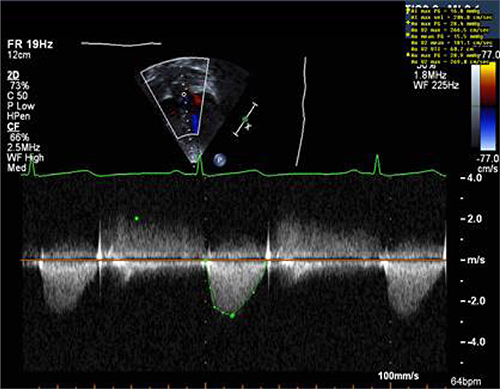

Figure 2: Sample of Doppler image and measurements obtained from suprasternal window in a patient with aortic stenosis.